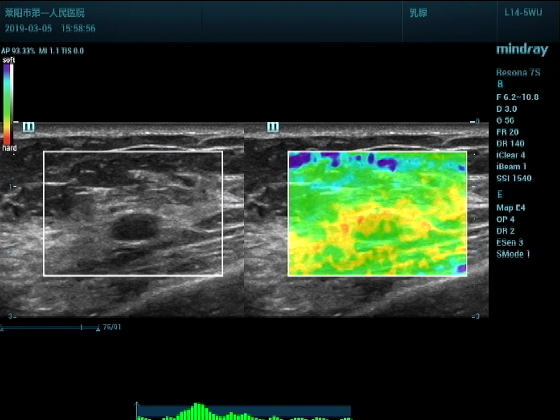

超声入门贴994--乳腺纤维瘤(弹性成像)